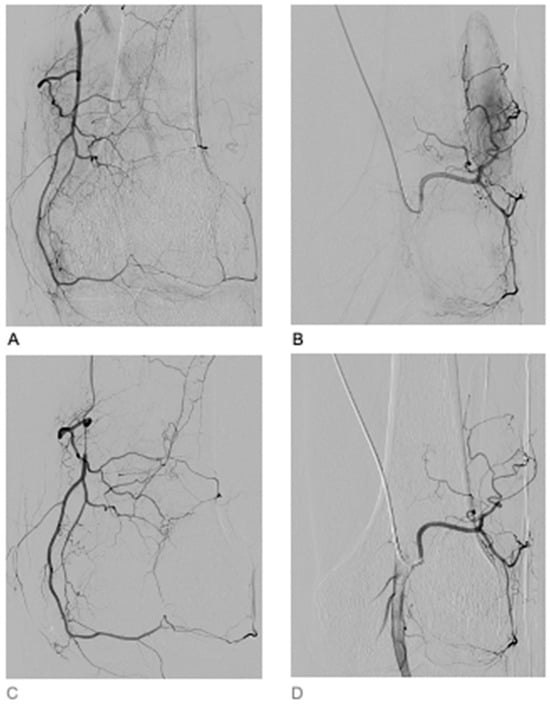

2. Case Presentation

3. Results